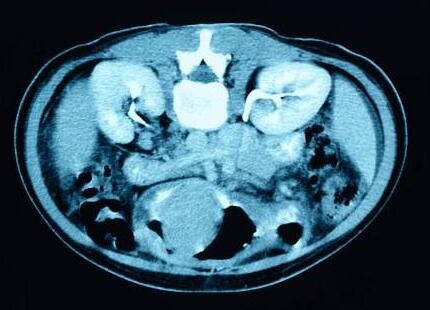

5.CT检查

CT检查是目前结石诊断的首选。CT检查可显示肾脏大小、轮廓、肾结石、肾积水、肾实质病变及肾实质剩余情况,还能鉴别肾囊肿或肾积水;可以辨认尿路以外引起的尿路梗阻病变的原因,如腹膜后肿瘤、盆腔肿瘤等;增强造影可了解肾脏的功能;对因结石引起的急性肾功能衰竭,CT能有助于诊断的确立。